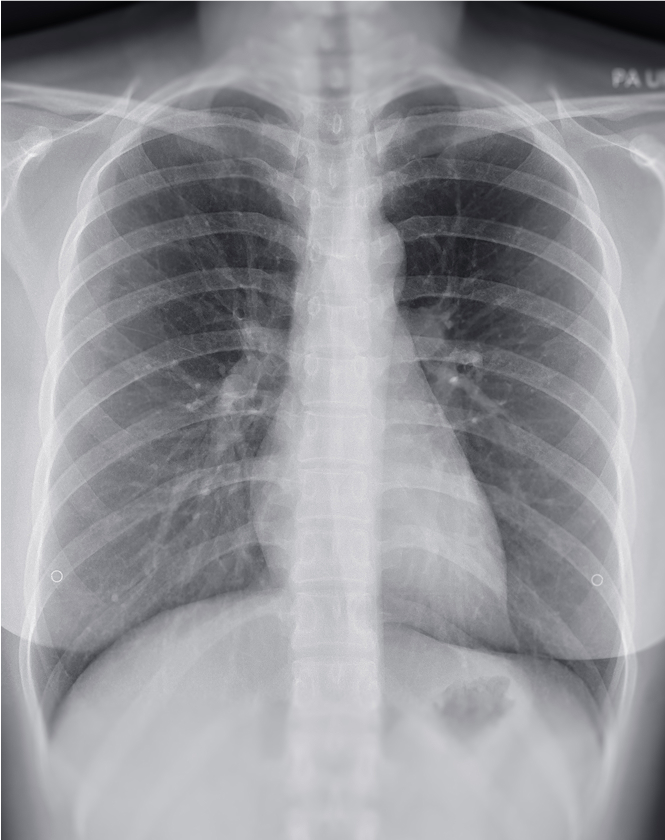

A comprehensive decision-support AI solution for chest X-rays, that detects up to 124 findings in under 20 seconds.